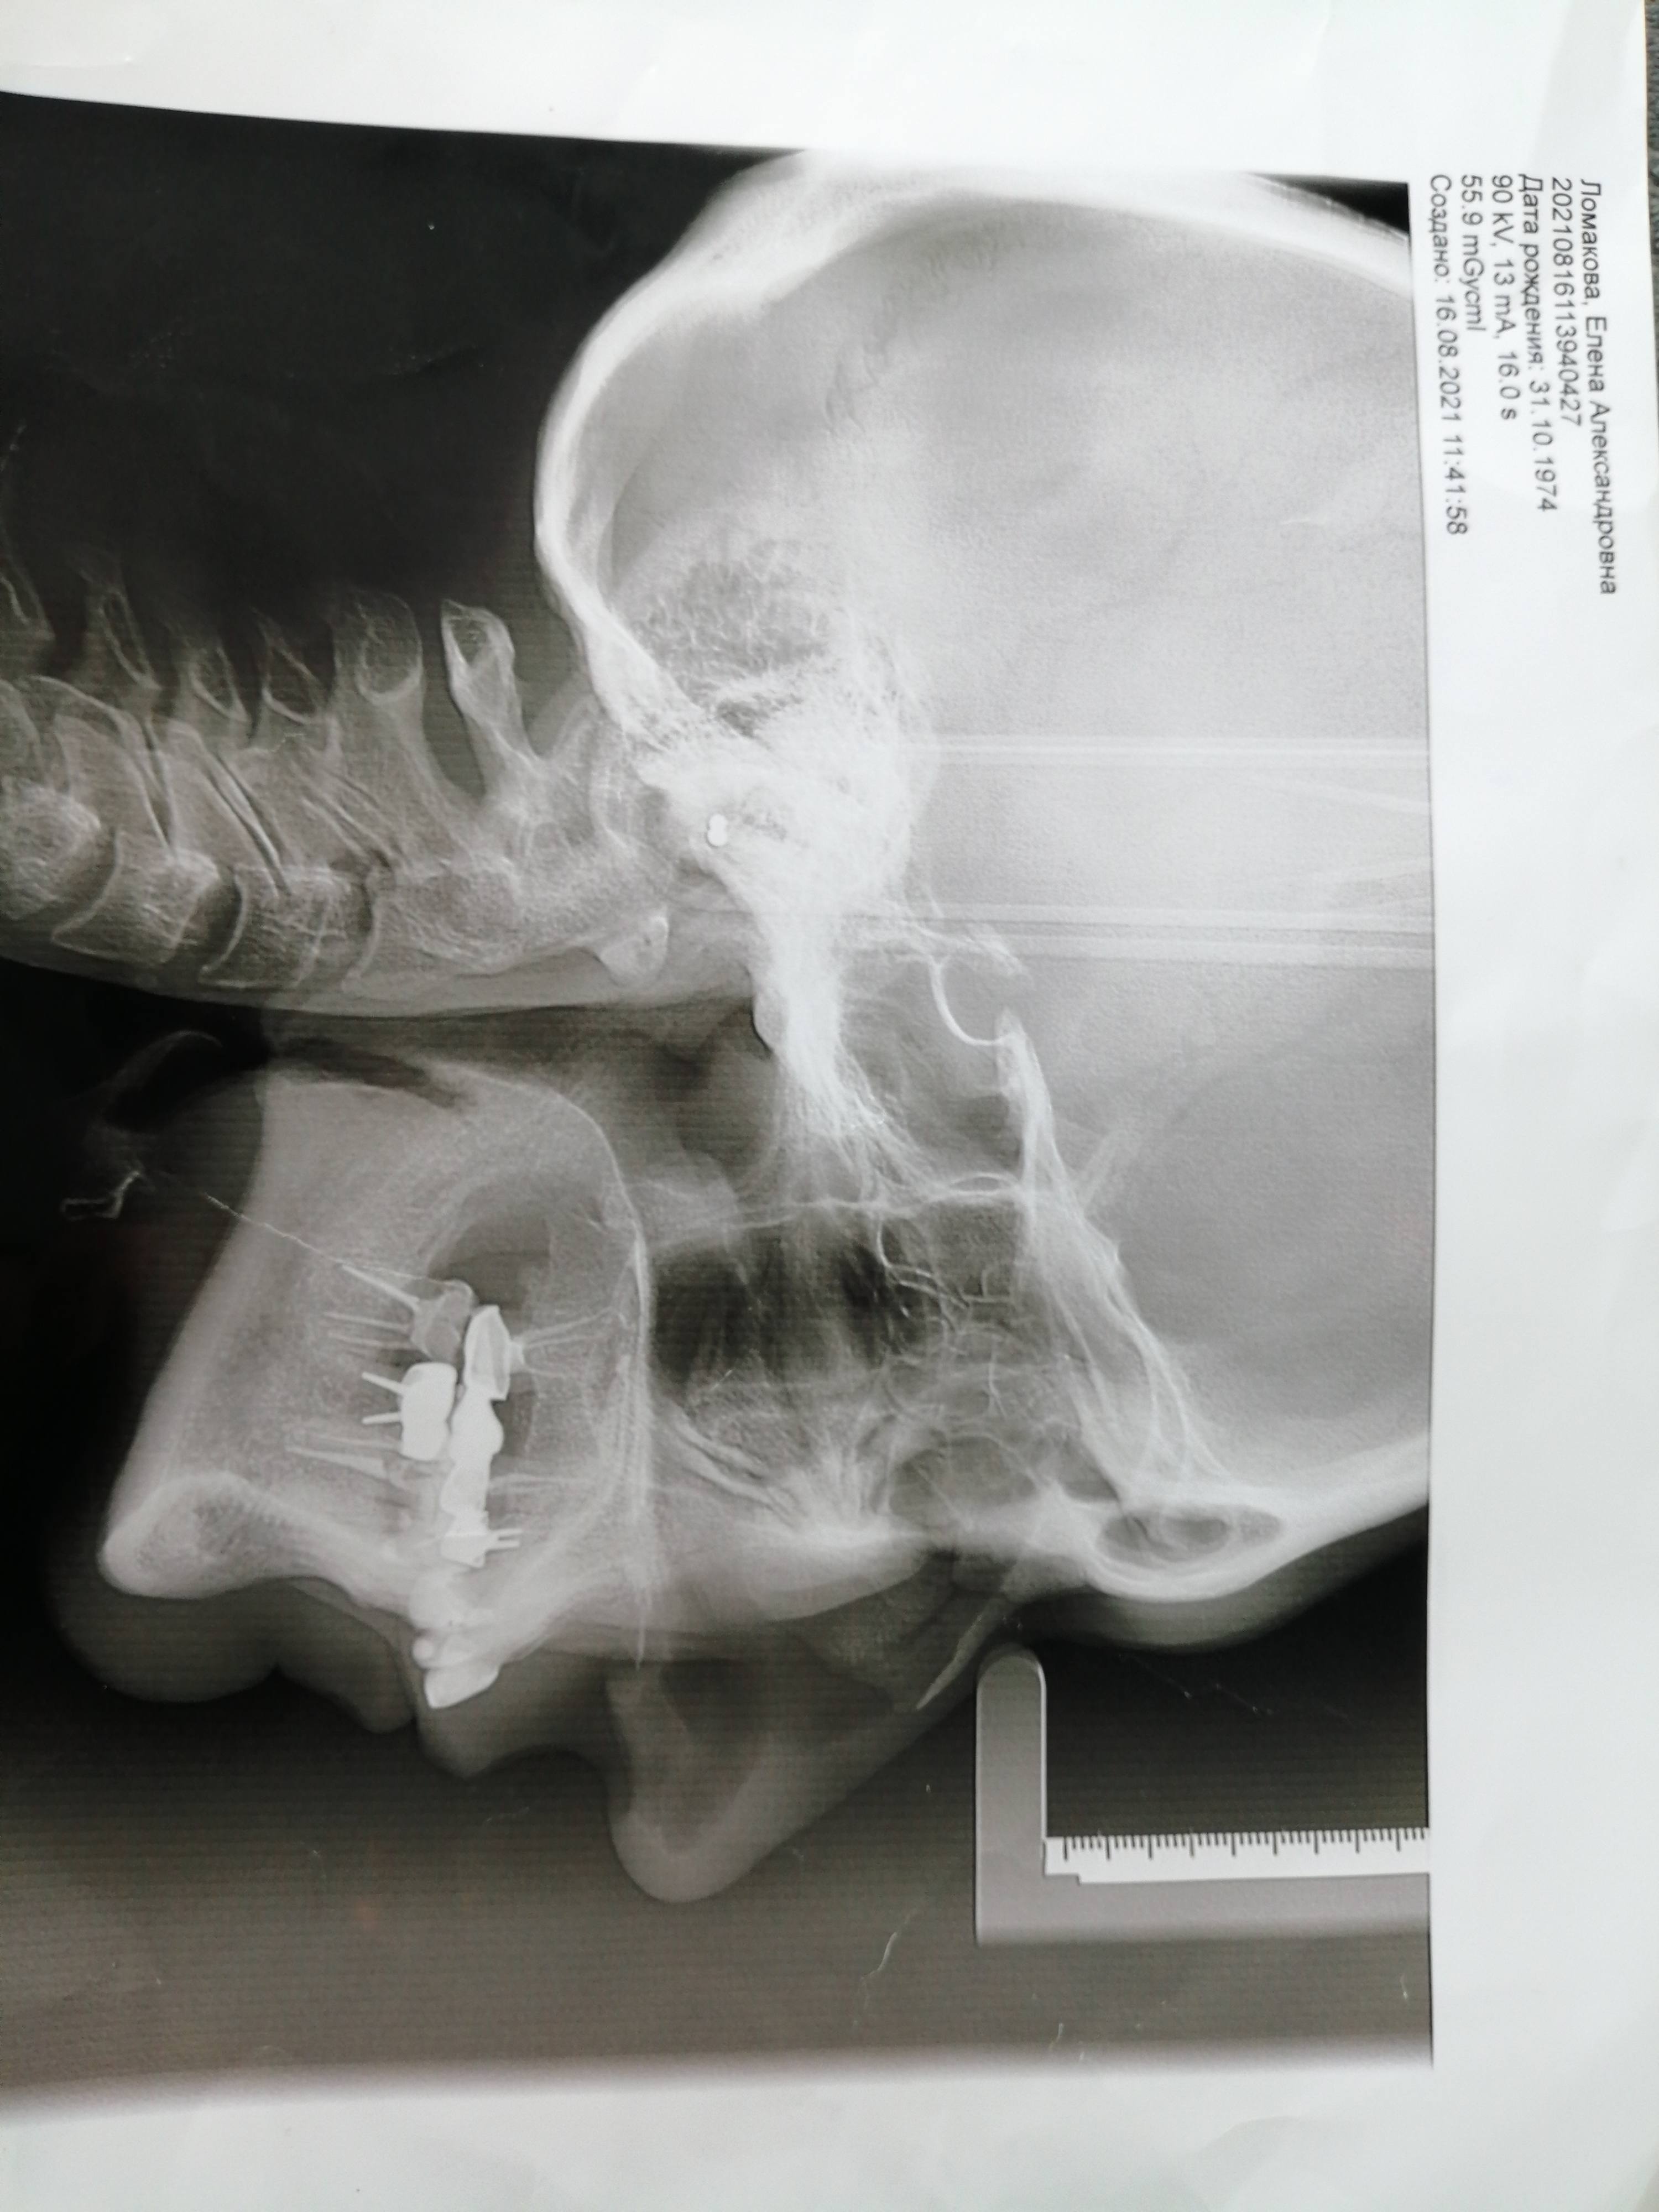

19 лет я получила травму-перелом верхней и нижней челюсти со смещением, были в травмпунке наложены шины на месяц и отправили домой, на сустав никто не обратил внимание. Через некоторое время начались проблемы с зубами, раскол коренных зубов. В итоге я потеряла все коренные зубы т. к.произошли изменения в суставе,на которые никто не обратил внимания. Затем было рекомендовано протезирование на коренные зубы, но оно не принесло результата, затем брекет система, она тоже без результата. Недавно я прошла консультацию челюстно-лицевого хирурга, и мне сказали что срочно нужно оперативное лечение с диагнозом Сочетанная деформация челюстей IIскелетный класс